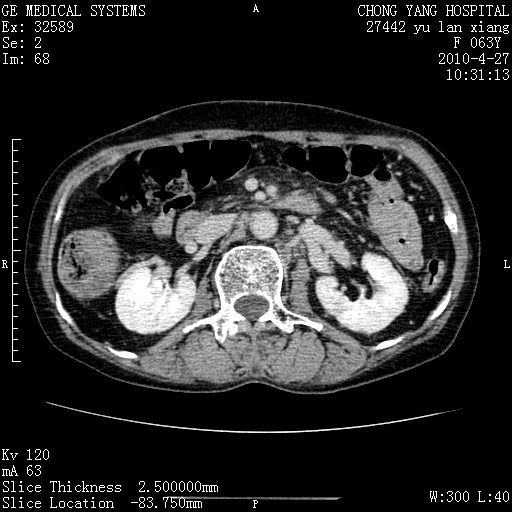

标题: CT26066:F63Y 上腹正中压痛半月,CA199:7400u/ml,MR示胰腺炎伴 [打印本页]

胰腺癌侵犯腹腔动脉干-分支、胃壁、左侧膈肌伴胰周及腹膜后淋巴结转移、胆囊切除术后。

胰腺癌侵犯腹腔动脉干-分支、胃壁、左侧膈肌伴胰周及腹膜后淋巴结转移、胆囊未显影。